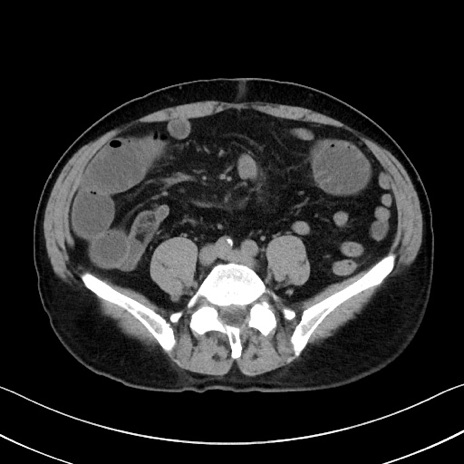

症例35(横断像)

冠状断像

【症例】70歳代 男性

【主訴】腹部膨満、嘔吐

【現病歴】昨日より腹部膨満感出現。本日増悪し、仙痛出現。嘔吐あり、受診。

【既往歴】糖尿病、胆摘後

【身体所見】BP 149/80mmHg、HR 74/min、BT 35.9℃、腹部:膨満、軟、圧痛なし。腸雑音減弱あり。上腹部正中切開瘢痕あり。

【データ】WBC 13500、CRP 1.72